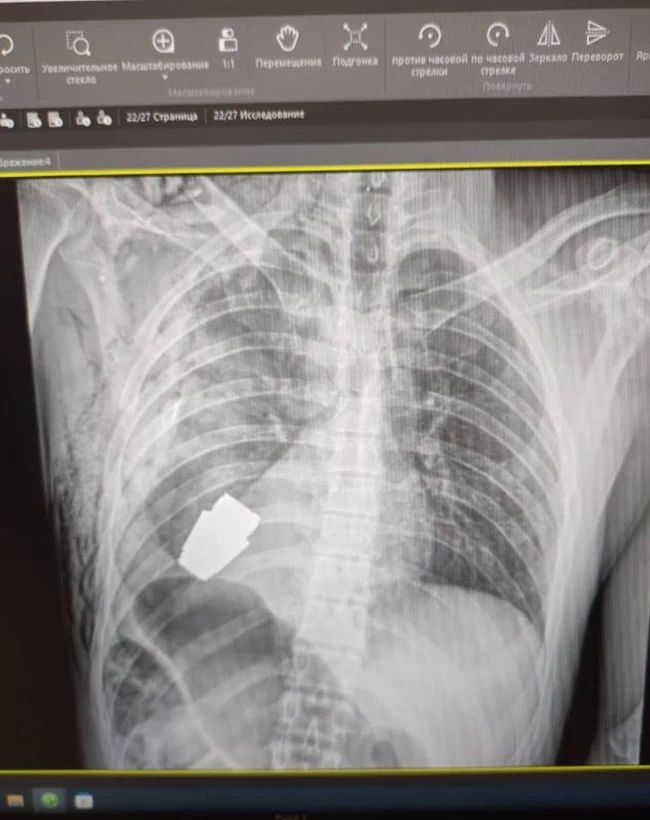

Στην ακτινογραφία φαίνεται η χειροβομβίδα τύπου VOG μέσα στο σώμα του στρατιώτη του πυροβολικού.

Πρόκειται για σοβιετικού τύπου χειροβομβίδα που προορίζεται για αυτόματο εκτοξευτή χειροβομβίδων.